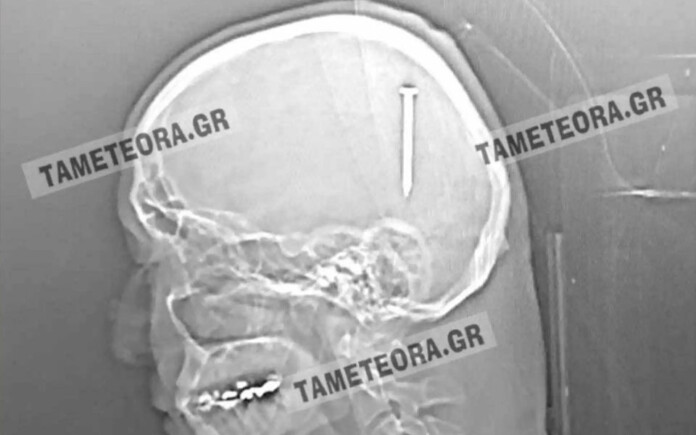

«Άγιο» είχε ένας άνδρας στη Καλαμπάκα, ο οποίος βρέθηκε ξαφνικά με ένα καρφί πέντε εκατοστών στο κεφάλι του

Όλα συνέβησαν όταν ο πρωταγωνιστής της ιστορίας, κατά τη διάρκεια εργασιών, ένιωσε ένα τράνταγμα, χωρίς όμως πόνο ή κάποιο άλλο σύμπτωμα.

Αρχικά μεταφέρθηκε στο Κέντρο Υγείας Καλαμπάκας και στη συνέχεια στο Γενικό Νοσοκομείο Τρικάλων. Από εκεί «πήρε τον δρόμο» για το Πανεπιστημιακό Νοσοκομείο Λάρισας, όπου του έγινε επέμβαση και του αφαιρέθηκε το καρφί με επιτυχία.

Σύμφωνα με την ιστοσελίδα tameteora.gr, ο Καλαμπακιώτης αναρρώνει υπό παρακολούθηση, αλλά εκτιμάται ότι δεν διατρέχει κανέναν κίνδυνο η υγεία του. Πρόκειται πραγματικά για ένα σπανιότατο περιστατικό, καθώς αν το καρφί βρισκόταν ελάχιστα χιλιοστά από το σημείο που σφηνώθηκε, θα ήταν πολύ επικίνδυνο για την υγεία του τραυματία.